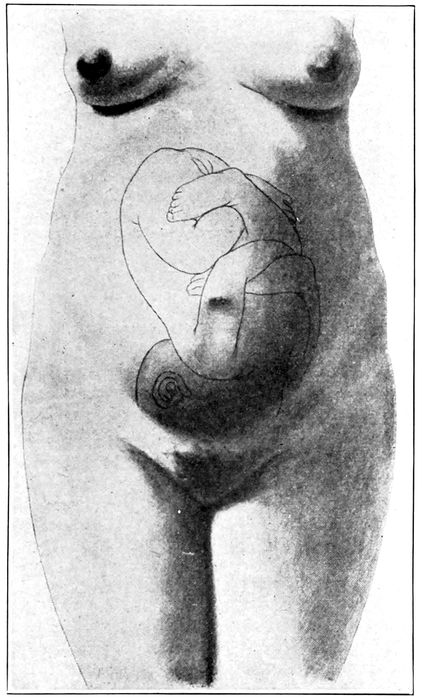

Fig. 20.—Normal attitude of fœtus (complete flexion). (Barbour.)